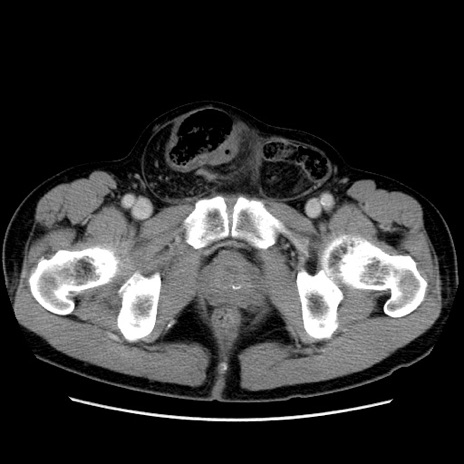

症例34(横断像)

【症例】60歳代 男性

【主訴】右鼠径部膨隆

【現病歴】1年程前より右鼠径部膨隆あり。自己にて還納可能だったため放置していた。3時間前より右鼠径部の脱出を認め、還納困難となり受診。

【身体所見】右鼠径部に小児頭大の膨隆あり。弾性硬であり、用手還納は困難。左鼠径部にも膨隆を認める。脱出はなし。

【データ】WBC 15500、CRP 測定なし